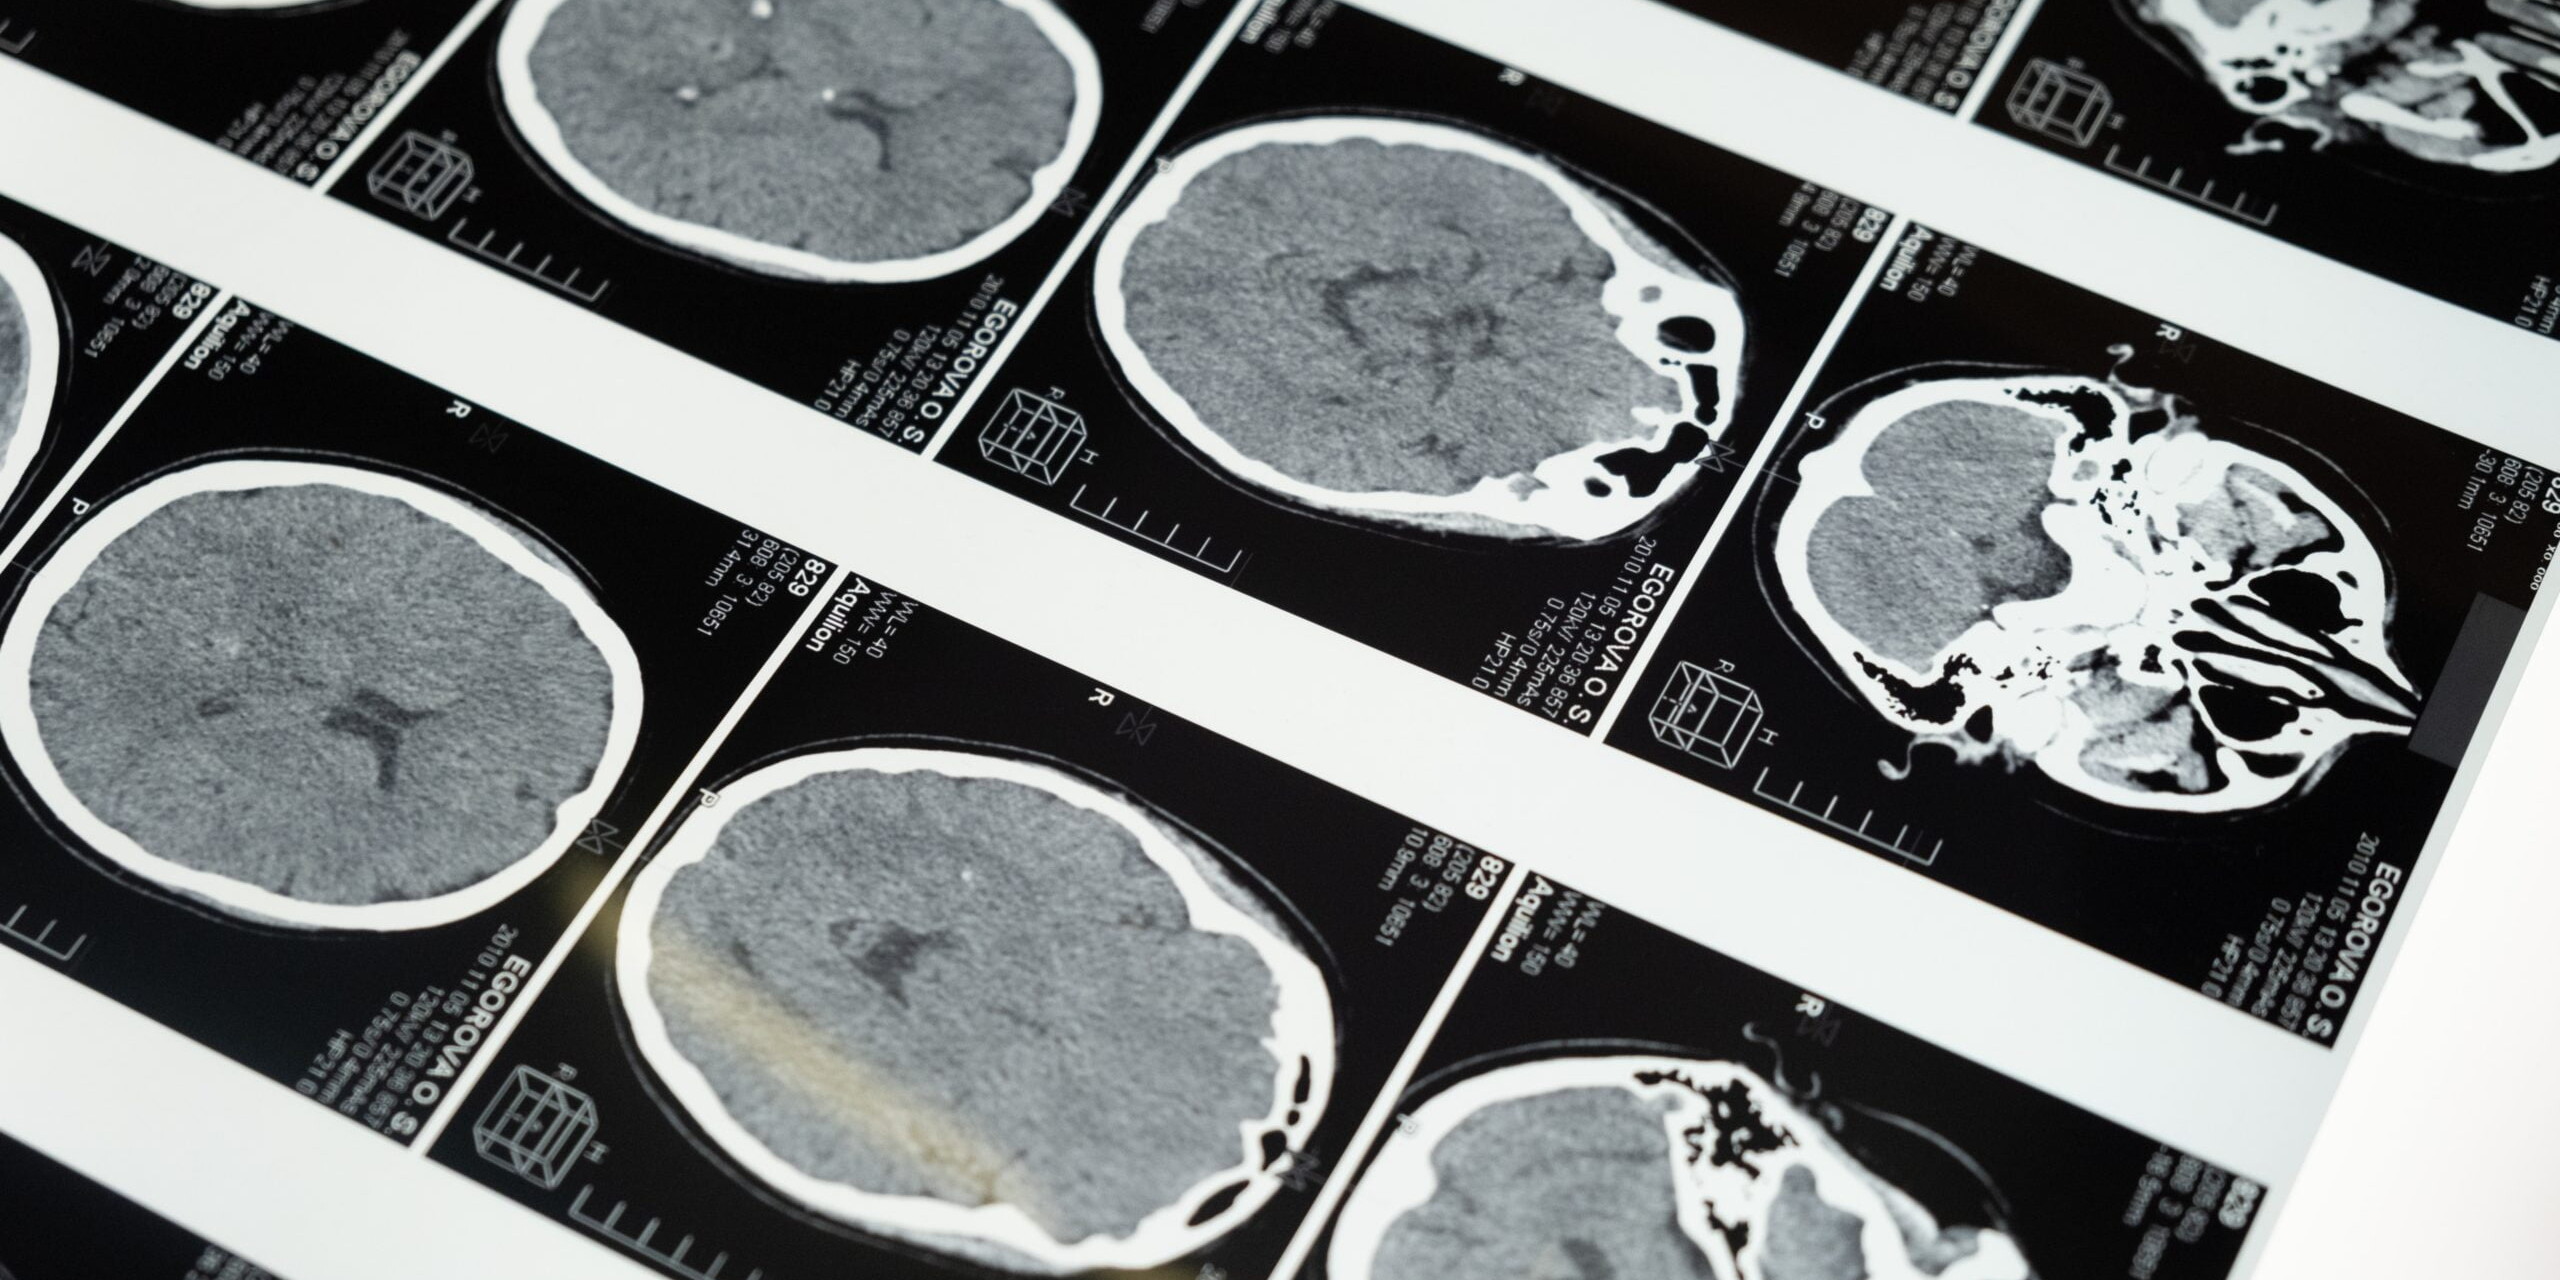

Is Brain Attack Or Stroke An Emergency?

Is Brain Attack Or Stroke An Emergency? Yes, a brain attack, commonly known as a stroke, is indeed…

Stroke Is The Number One Cause Of Disability

Did you know that a brain attack, better known as a stroke, strikes someone every 40 seconds around…